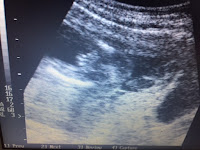

It was market day and Dana, the animal lover and also now known at La Cabra Huera (White Goat) befriended several baskets of live chickens. Once we arrived in Santa Eulalia the waiting room was full and after delivering the aformentioned supplies, we went right to work. Dana saw over 30 woman and children with a variety of complaints. Lisa (hence named Colibri Brilliante) saw about the same numero of pregnant women and did quite a few 1st trimester dating scans. Drs Suzana also worked hard alongside in her own consultorio.

The little old Providence Milwaukie US Machine performed like a champ, we did over 30 US including checking for a hemoperitoneum on a patient who had been battered by her partner. She has no signs of injury, was the last patient of our day and reminded us of how domestic violence affects every community.